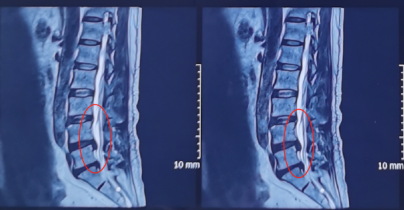

来到陕西冶金医院神经脊柱科后,由张少华主任、熊东主任接诊,经过各项检查后发现他在腰3/4、腰4/5、腰5/骶1都有不同程度的突出,尤其是在腰4/5突出非常严重。鉴于曹先生主要的症状表现和影像学等检查结合,判断腰4/5为主要责任节段,并建议尽快进行微创手术,给神经进行解压。

术前影像学资料